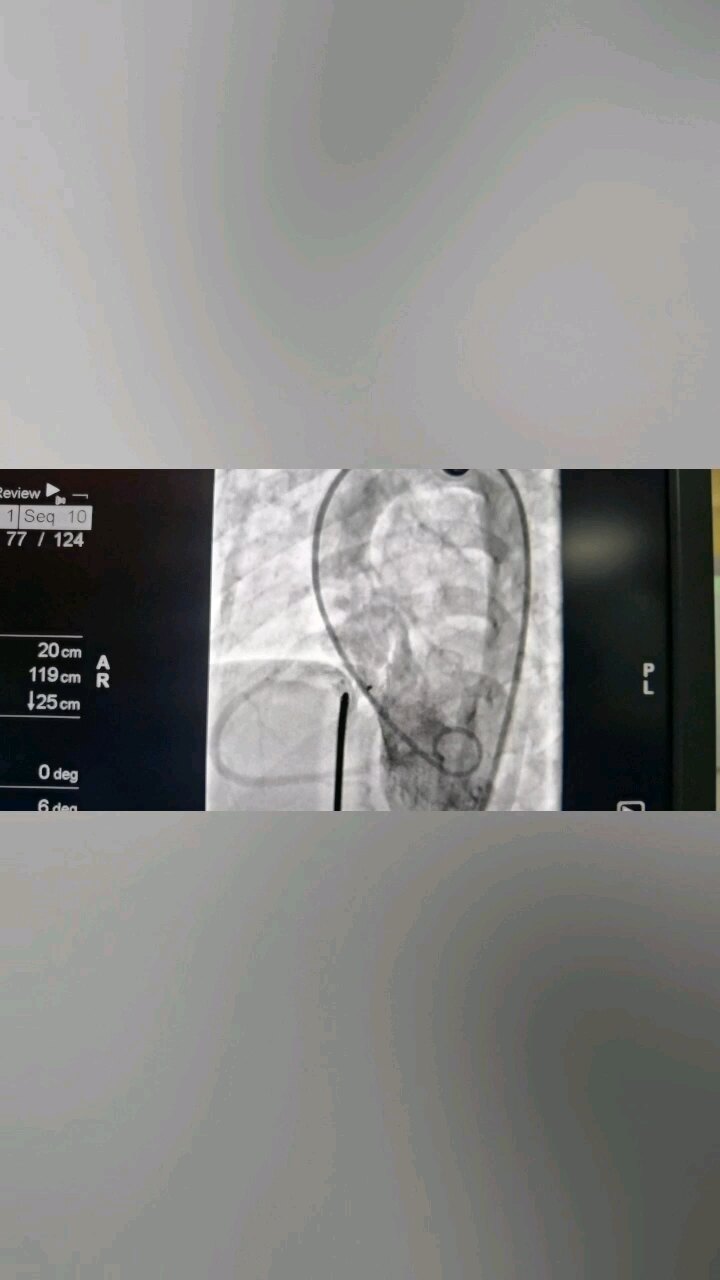

室缺封堵 先心病 免费 卵圆孔封堵 可降解封堵器